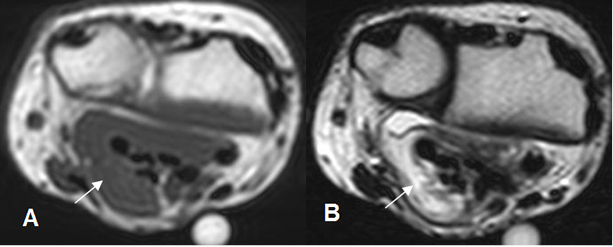

Fig 95 A. Fibromatosis.

A: RM axial en T1 y B: RM axial en T2. Presencia de tejido inflamatorio agudo hipointenso en T1 e hiperintenso en T2, que rodea los tendones flexores, a nivel de la muñeca.